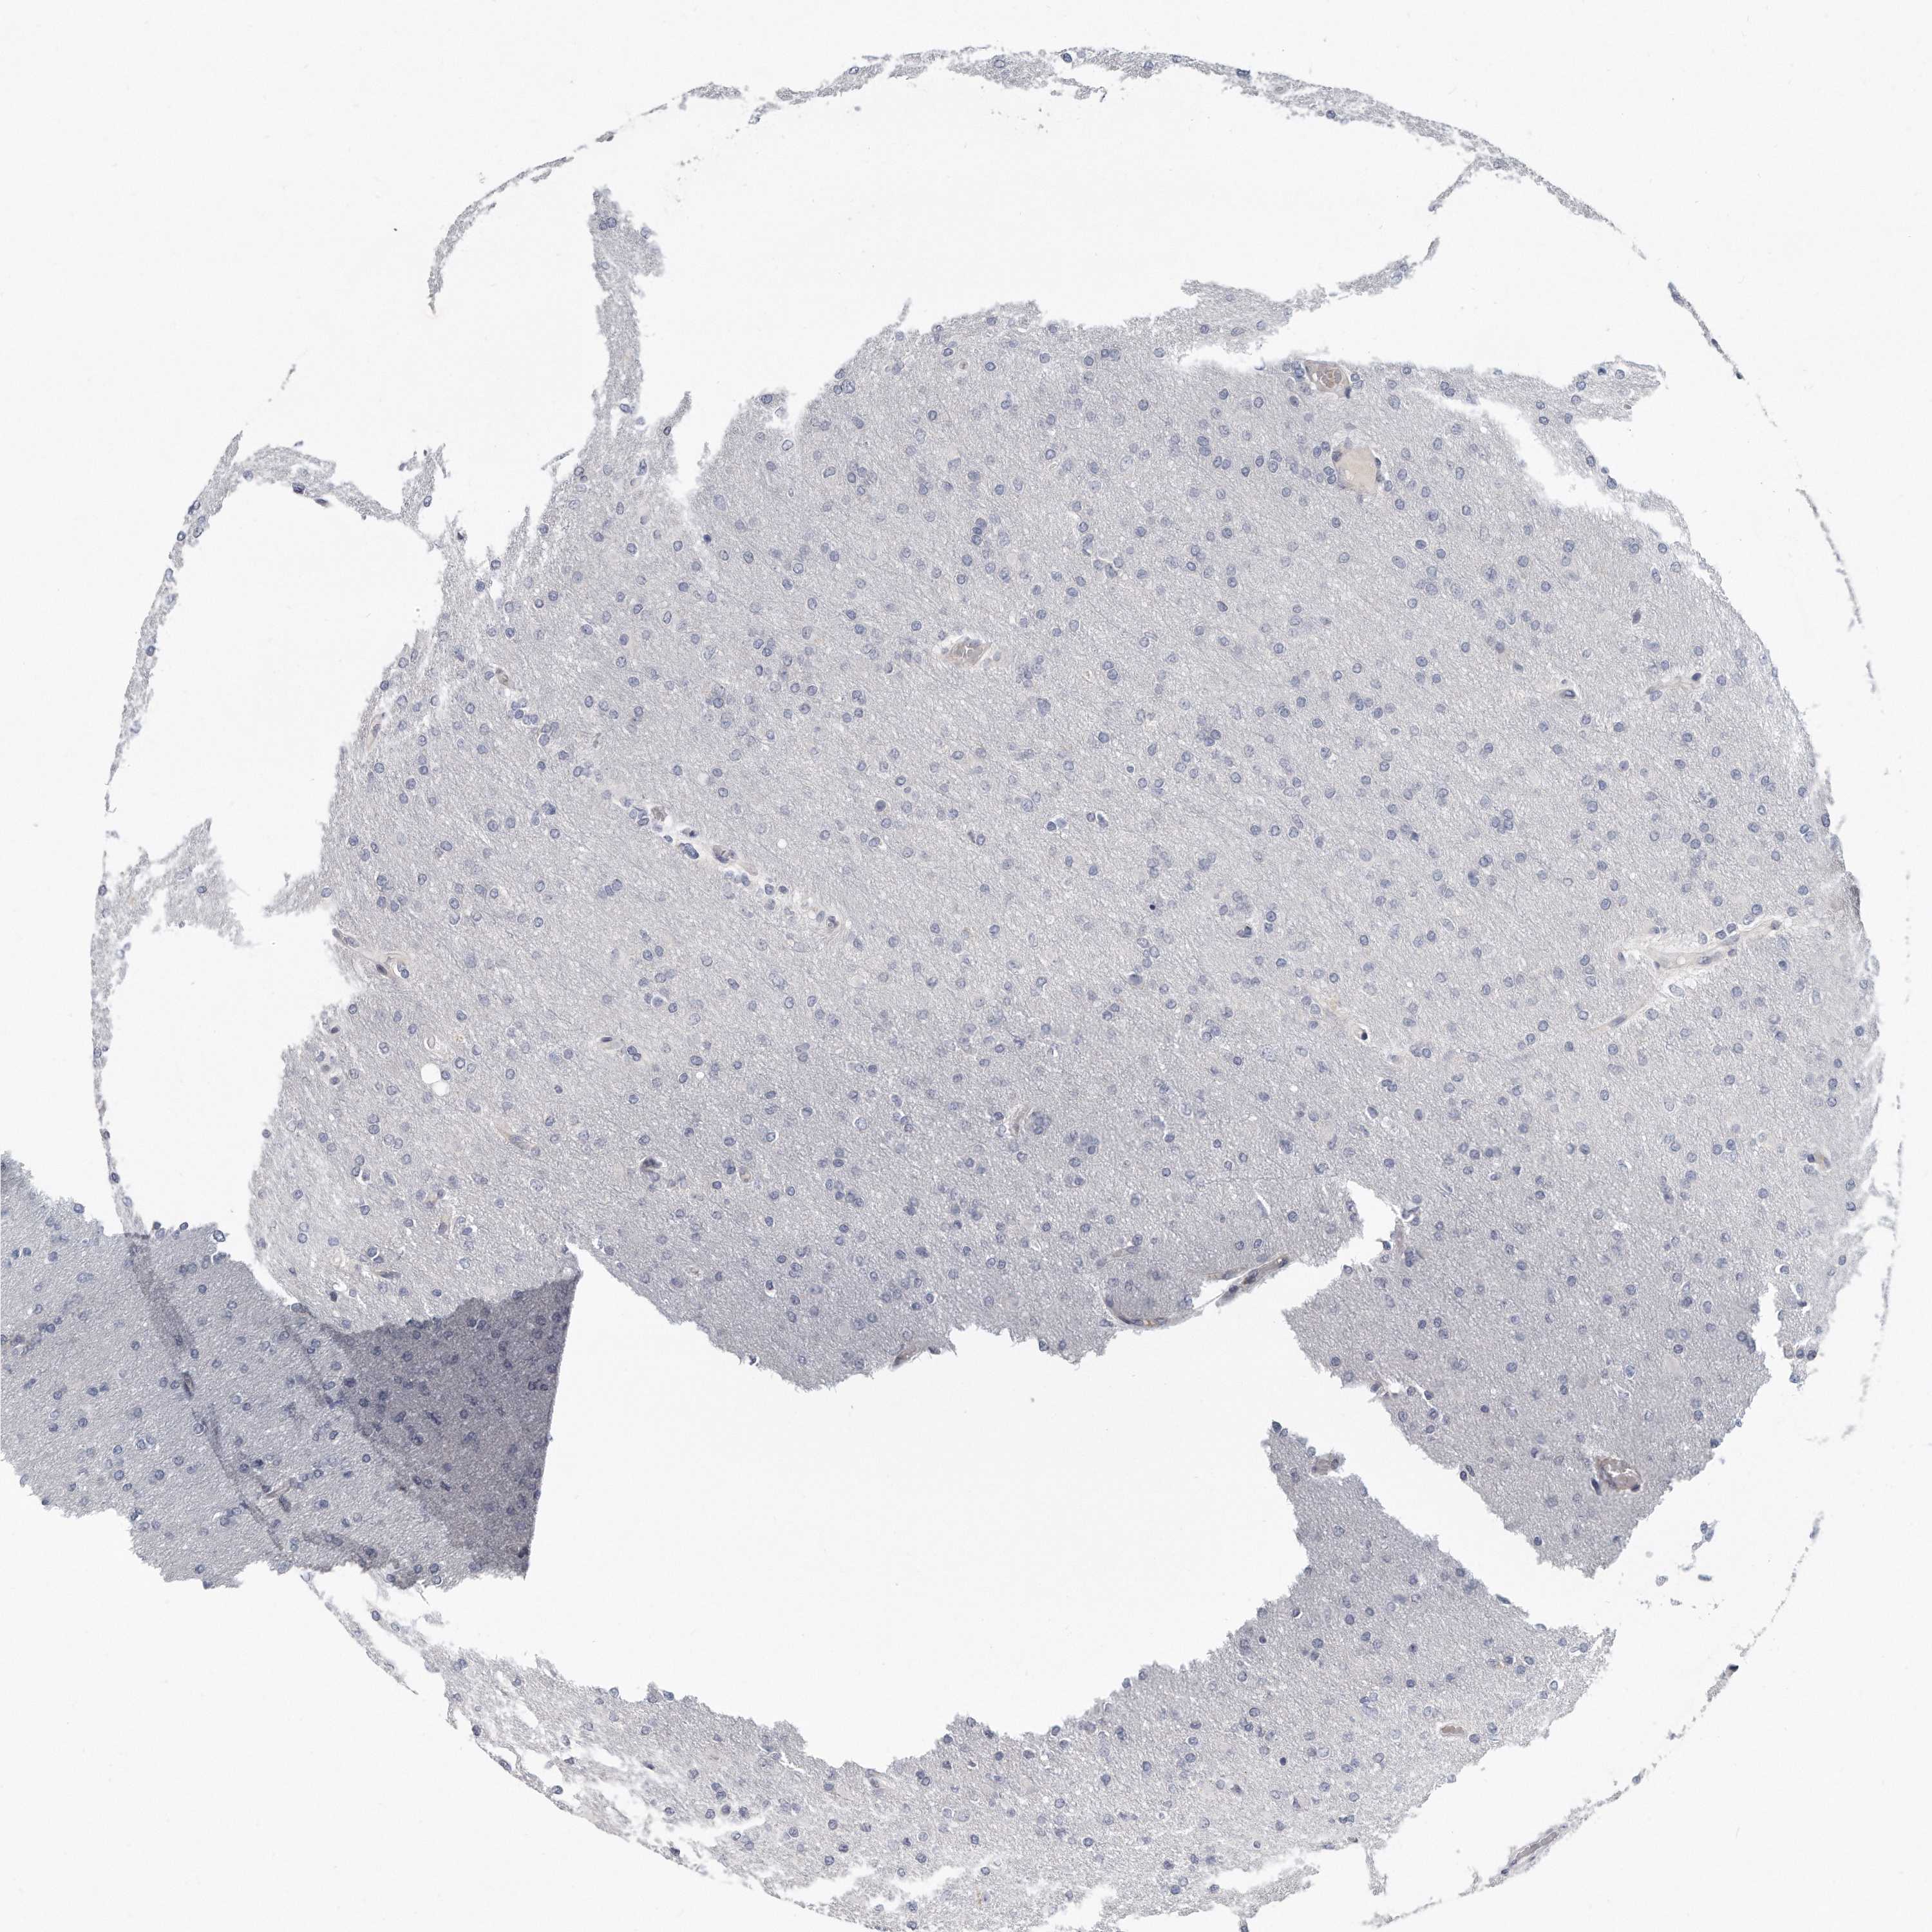

GLIOMA - Protein expressioni

A mouse-over function shows sample information and annotation data. Click on an image to view it in a full screen mode. Samples can be filtered based on level of antibody staining by selecting one or several of the following categories: high, medium, low and not detected. The assay and annotation is described here.

Note that samples used for immunohistochemistry by the Human Protein Atlas do not correspond to samples in the TCGA dataset.

Antibody stainingi

Antibody staining in the annotated cell types in the current human tissue is reported as not detected, low, medium, or high, based on conventional immunohistochemistry profiling in selected tissues. This score is based on the combination of the staining intensity and fraction of stained cells.

Each image is clickable and will lead to virtual microscopy that enables deeper exploration of all samples and also displays staining intensity scores, fraction scores and subcellular localization as well as patient and tissue information for each sample.

Antibody HPA028152

Staining

High

Medium

Low

Not detected

Intensity

Strong

Moderate

Weak

Negative

Quantity

>75%

75%-25%

<25%

None

Location

Nuclear

Cytoplasmic/membranous

Cytoplasmic/membranous,nuclear

Glioma, malignant, High grade

Glioma, malignant, Low grade

Glioblastoma, NOS